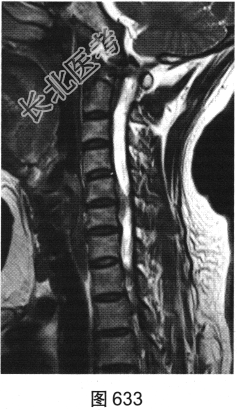

- [材料题] 患者女性,49岁,颈部胀痛伴双手麻木3天。MRI检查见图632~图637。

- 多项选择题1.患者MRI图片有哪些阳性征象( )

A、同水平硬膜囊及脊髓明显受压

B、病变与硬膜夹角为钝角

C、病变呈环形强化,中心未见明显强化

D、病变在髓外硬膜下

E、病变跨越右侧椎间孔,呈哑铃状改变

F、C

水平硬膜外梭形软组织信号

- 多项选择题2.根据MRI表现,患者可能的诊断是( )

A、脊柱淋巴瘤

B、椎间盘脱出、髓核游离

C、神经纤维瘤

D、后纵韧带骨化

E、神经鞘瘤

F、硬膜外血肿